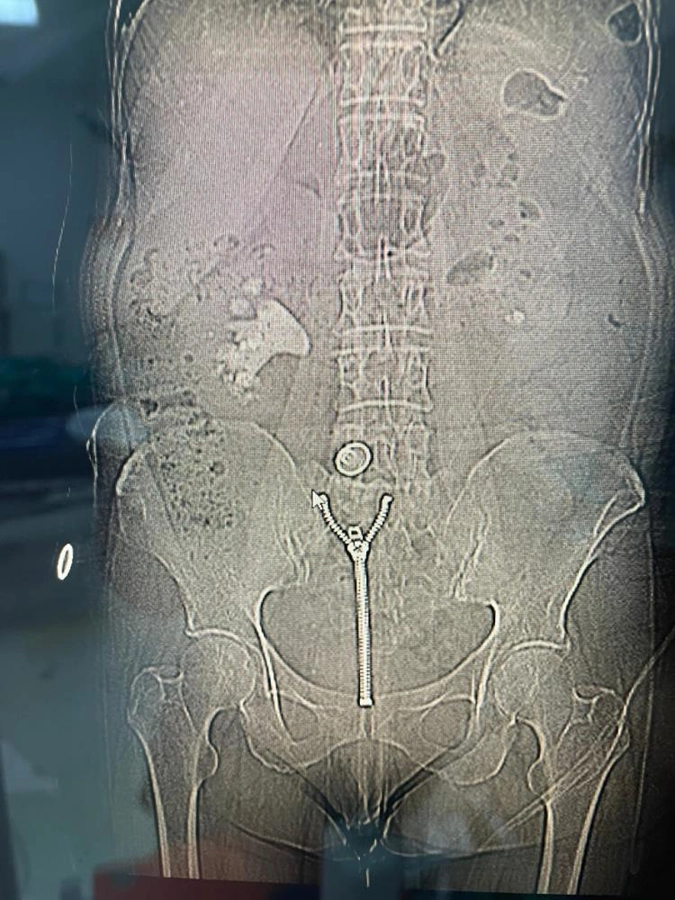

Malatya Eğitim ve Araştırma Hastanesi'nde 58 yaşındaki Ülkü Sabaner'in böbreğini tamamen dolduran 8 santimetrelik "geyik boynuzu" (staghorn) böbrek taşı, kapalı yöntemle gerçekleştirilen başarılı bir operasyonla çıkarıldı.

Sağ yan ağrısı şikâyetiyle hastaneye başvuran Sabaner'in yapılan tetkiklerinde, sağ böbreğini neredeyse tamamen dolduran büyük boyutlu bir taş olduğu belirlendi. Daha önce de böbrek taşı nedeniyle tedavi gören ve çocukluk yaşlarından itibaren taş hastalığıyla mücadele ettiği öğrenilen hastaya, Üroloji Kliniği uzmanları tarafından kapalı ameliyat önerildi.

Operasyonu gerçekleştiren Üroloji Kliniği Uzmanı Dr. Mehmet Levent Akbulut, taşın büyüklüğüne dikkat çekerek, "Hastamızın böbreğinde yaklaşık 8 santimetre çapında büyük bir taş vardı. Tıpta bu tabloya ‘staghorn', yani geyik boynuzu taşı diyoruz. Eğer bu taş alınmasaydı, böbrek fonksiyonunu tamamen kaybedebilirdi. Biz de perkütan nefrolitotomi adını verdiğimiz kapalı yöntemi tercih ettik. Tomografi yardımıyla planlama yaparak, böbreğe küçük bir delikten girip taşı parçalara ayırarak tamamen temizledik. Ameliyat sonrası hastamızın böbreği taşsız hale getirildi" dedi. Dr. Akbulut, söz konusu yöntemin açık ameliyata göre çok daha hızlı iyileşme süreci sağladığını ve bu tür kompleks operasyonların Malatya'da başarıyla gerçekleştirilebildiğini belirtti.

"Yarım su bardağı kadar taş çıktı"

Başarılı operasyon sonrası kısa sürede sağlığına kavuşan Ülkü Sabaner, "Bir akşam şiddetli sancıyla acile başvurdum. Yapılan kontrollerde büyük bir taşım olduğu ortaya çıktı. Doktorlarım kapalı yöntemle ameliyat edilebileceğini söylediler. Pazartesi günü ameliyat oldum, üç gün sonra taburcu oldum. Çıkan taş neredeyse yarım su bardağı kadardı. Açık ameliyata göre çok daha kolay bir süreçti. Bir hafta içinde normal hayatıma geri döndüm. Başta doktorum olmak üzere tüm sağlık çalışanlarına teşekkür ediyorum." ifadelerini kullandı